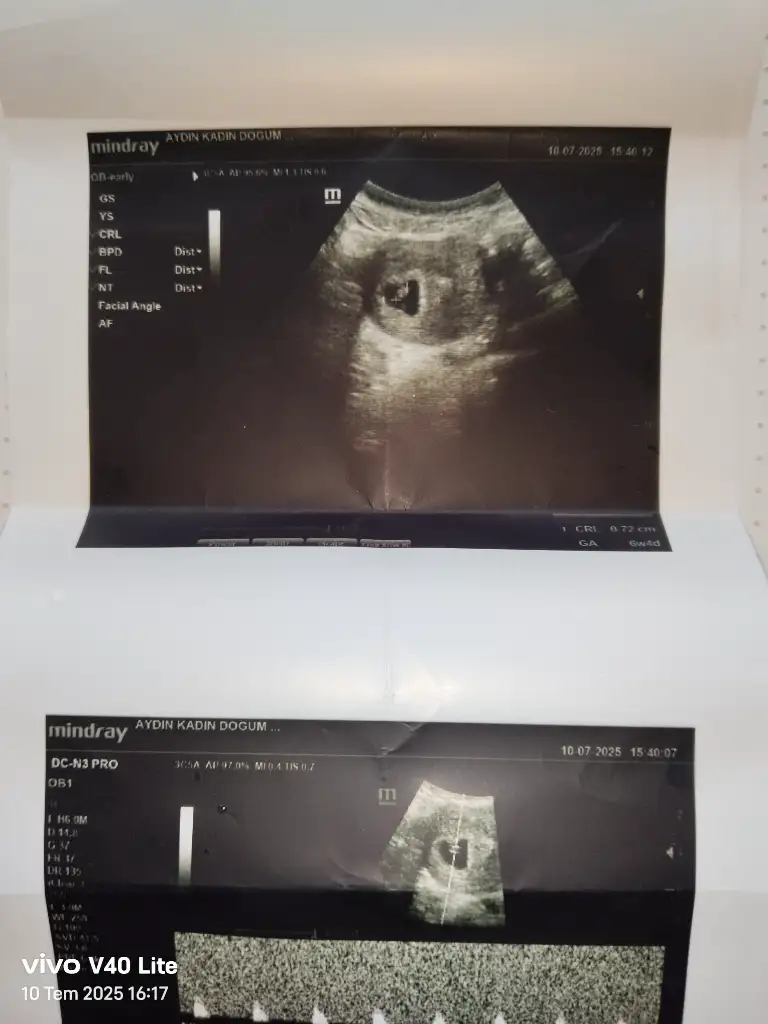

Ayy çok sevindimMerhaba, doktor kontrolünden çıktım şimdi. Kesemiz göründüHaftası ile uyumlu dedi doktor 8mm. 4+5'im şu anda. 17 Temmuz'da kalp atışı için çağırdı